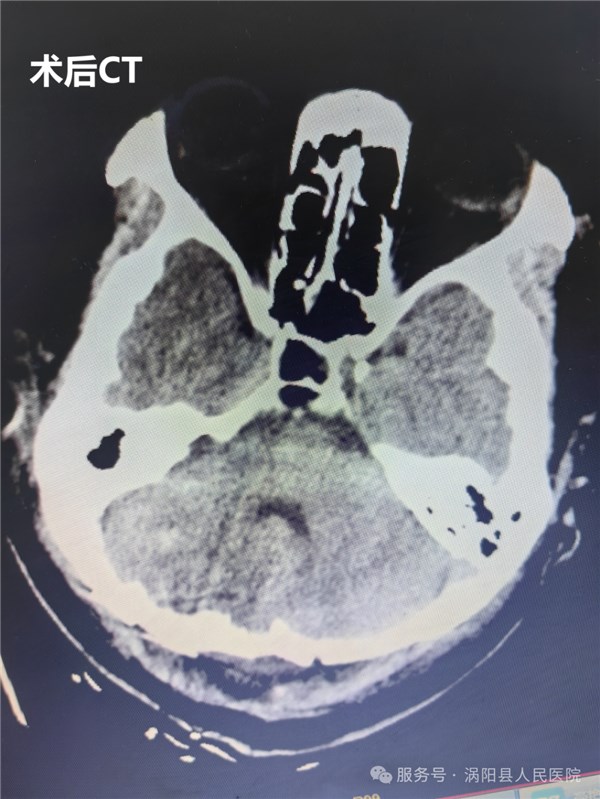

3月13日,手术正式开展。在全身麻醉下,由神经外科主任医师周维广、王超领衔的手术团队,在手术显微镜下精准施治。该手术采用后正中入路,手术视野深、操作空间狭小,对主刀医生的心理素质和专业技术都是极大考验。手术团队凭借丰富的临床经验、娴熟的显微外科技术,历经6小时细致操作,成功完整切除病变组织,并将标本送检病理检查。术后复查CT显示,手术效果理想,患者颅内情况良好。